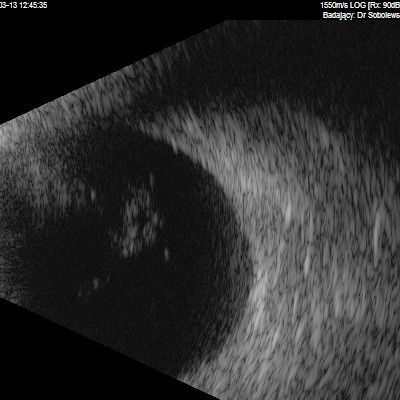

Dziwne mętów

Przedstawiane obrazy ultrasonograficzne® są oryginalne i pochodzą z mojej praktyki lekarskiej